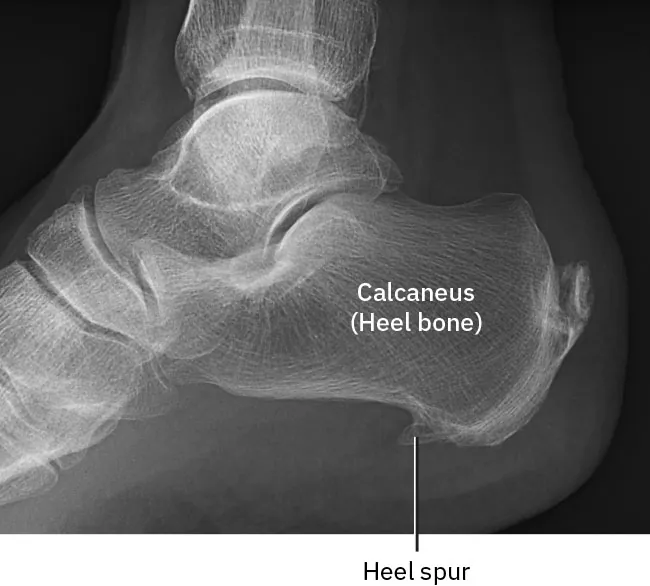

• a bony projection that develops along bone edges, known as a bone spur (Figure 13.7); and

X-ray of bone spur, labeling Calcaneus (Heel Bone) and Heel Spur

Figure 13.7 This x-ray image shows a bone spur that has developed on the heel of the foot. (credit: “Achilles insertional calcific tendinosis” by Mikael Haggström/Wikimedia Commons, CC0)